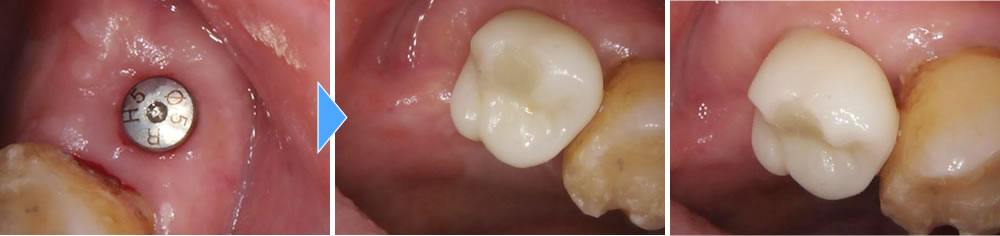

上部構造の装着・治療完了

年齢が高くなると傷の治りも遅くなってしまうので通常より少し長く4ヵ月おき、しっかりと骨とオステオインテグレーションしている事を確認し、上部に歯を作成しました。結果しっかりと噛む事ができ満足して頂く事ができました。